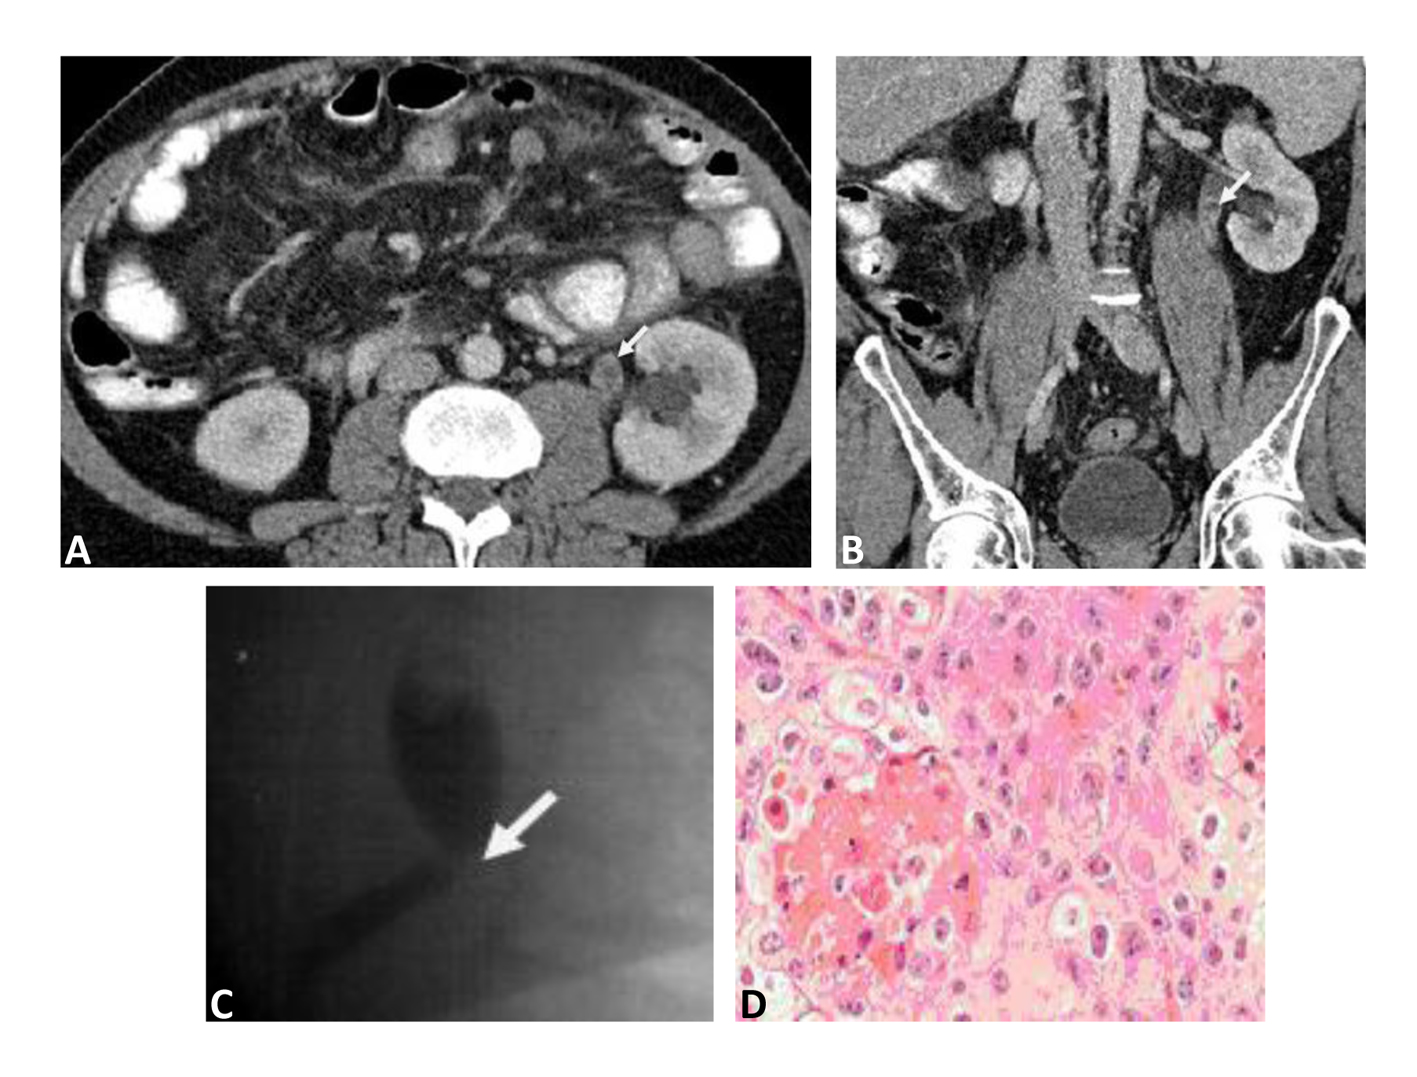

On contrast Computerized Tomography (CT) of the abdomen and pelvis showed a filling defect on the upper third of left ureter just below uretero-pelvic junction (UPJ) with proximal ureteric dilatation concerning for ureteric carcinoma (Fig. 1A, B ). No evidence of distant metastasis was found. To further delineate the ureteric filling defect, flexible ureteroscopy and retrograde study was subsequently performed and revealed a filling defect below the left UPJ (Fig. 1C). This lesion was directly visualized by flexible ureteroscope and revealed 2 cm polypoid like tumour just below the left UPJ. Direct biopsy and/or brush cytology of this tumour was failed due to its excessive mobility of the lesion.

![]() Click for large image | Figure 1. A: Transverse section Contrast Computerized Tomography (CT) image, a filling defect is demonstrated in the left upper ureter (just below the uretero-pelvic junction) (marked by white arrow). B: Sagittal section Contrast Computerized Tomography (CT) image, a filling defect is demonstrated in the left upper ureter (just below the uretero-pelvic junction) (marked by white arrow). C: Retrograde contrast study of left ureter, a filing defect is shown just below the uretero-pelvic junction (marked by white arrow). D: A high power (20 × objectives) of squamous cell carcinoma of the left ureter, nests of squamous cells with hyperchromatic nuclei and prominent keratin production (Haematoxylin and Eosin stain). |

After multidisciplinary team meeting and thorough discussion with the patient in regards to the therapeutics modalities available. This patient opted to undergo an open left radical nephro-ureterectomy which was subsequently performed successfully. Histology of the specimen showed urothelial solid tumour 18 × 10 mm with squamous differentiation. No involvement of lamina properia (pT1N0M0) or vascular/lymphatic invasions (Fig. 1D). Post operatively, the patient made an uncomplicated recovery and subsequently discharged home. On his first 3-monthly follow-up visit, patient was clinically well and all his abdominal wounds have healed. To date, cystoscopical examination of patient’s urinary bladder showed also no evidence of tumour recurrence. In addition, CT follow-up revealed no evidence of local recurrence or distant metastasis.